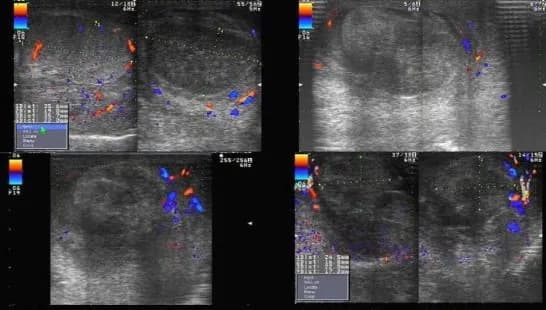

4. Hình ảnh xoắn tinh hoàn trên siêu âm Doppler màu

- Giai đoạn cấp tính (1-6 giờ):

- Giảm hoặc không tưới máu tinh hoàn: Trong giai đoạn sớm của xoắn tinh hoàn, siêu âm Doppler màu có thể cho thấy giảm hoặc không có dòng chảy máu trong tinh hoàn bị xoắn.

- Dấu hiệu xoáy nước ở thừng tinh: Dấu hiệu xoáy nước là một dấu hiệu quan trọng cho thấy sự xoắn của thừng tinh.

- Giai đoạn muộn (> 24 giờ):

- Hồi âm không đồng nhất: Khi xoắn tinh hoàn kéo dài, tinh hoàn có thể bị tổn thương và có hồi âm không đồng nhất trên siêu âm.

- Tăng tưới máu mô xung quanh: Trong một số trường hợp, có thể thấy tăng tưới máu ở các mô xung quanh tinh hoàn bị xoắn do phản ứng viêm.